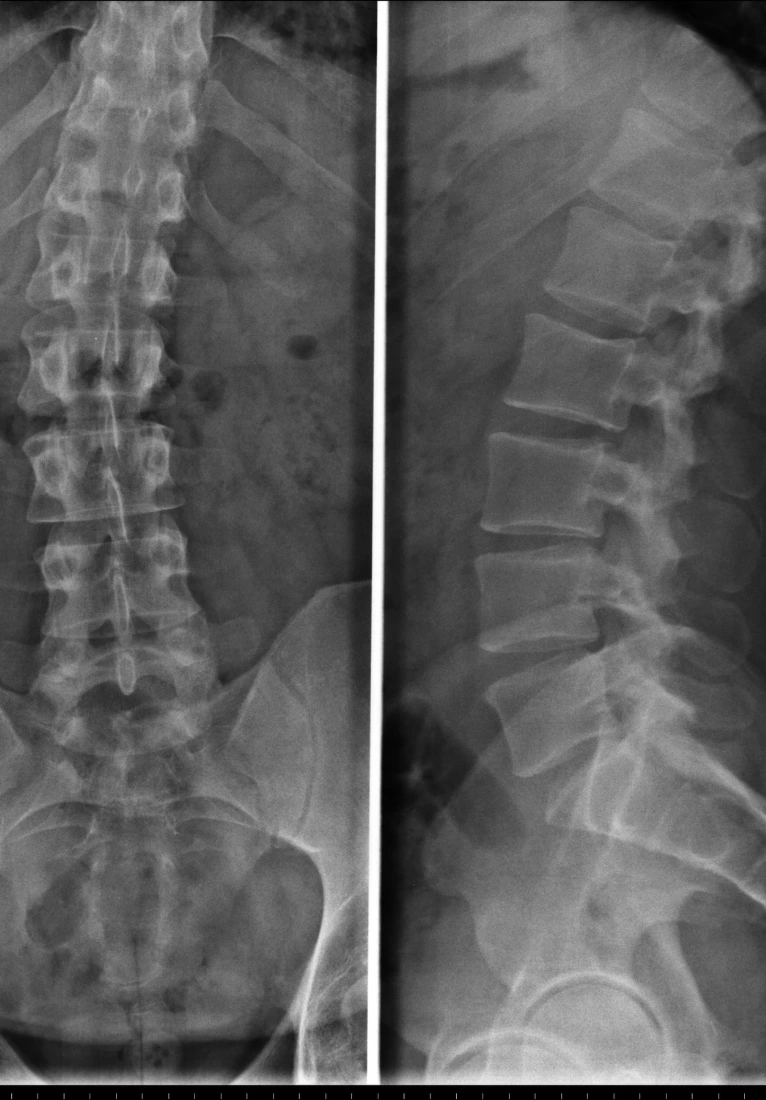

Chiropractors take x-rays to see the internal condition of the spine. X-rays also reveal if there are any underlying spinal disorders, such as arthritis of the spine, abnormal development, disc disorders, bone spurs, and spinal deterioration.

Having an x-ray taken before any adjustment helps chiropractors make a correct diagnosis. Combining x-rays with other exams will benefit the patient ultimately.